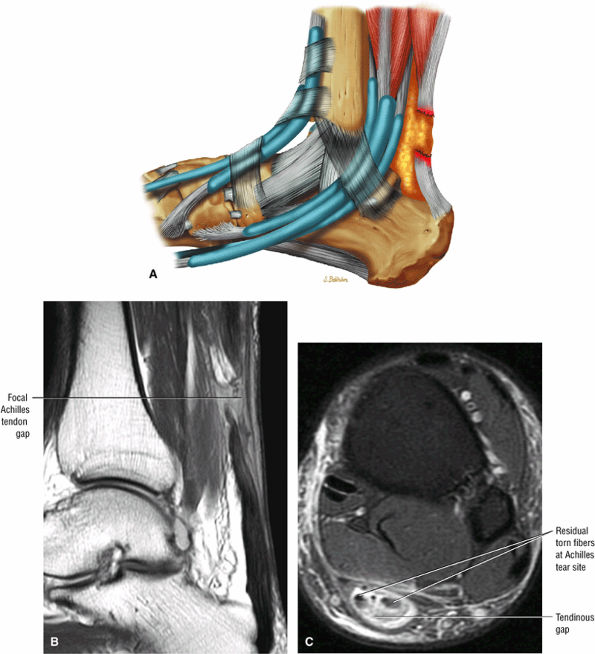

FIGURE 5.124 ● Focal complete tear of the Achilles tendon with less than 3 cm of retraction. (A) Lateral color graphic. (B) Sagittal T1-weighted image. (C) Axial FS PD FSE image.

Type 1: Partial ruptures affecting 50% or less of the tendon (Fig. 5.123)

Type 2: Complete ruptures with a tendinous gap of 3 cm or less (Fig. 5.124)

A fluid-filled gap with or without interposed fat at the tear site in complete tendinous disruptions with discontinuity

Fraying or corkscrewing (see Fig. 5.123) of the tendon edges associated with proximal tendon retraction

In the absence of overlapping tendon edges, no tendon fibers can be seen at the tear site on axial images.

Tendon disruption with discontinuity and a wavy retracted tendon

Associated hemorrhage or edema in intratendinous or peritendinous soft tissues on axial or sagittal images

Complete tears demonstrate a hyperintense fluid-filled tendinous gap.